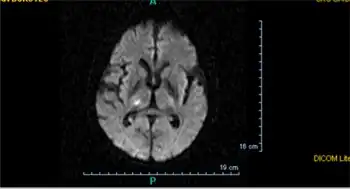

A silent lacunar infarction (SLI) is one type of silent stroke which usually shows no identifiable outward symptoms, and is thus termed "silent." Because stroke is a clinical diagnosis (that is, it is defined by clinical symptoms), there is debate about whether SLI are considered to be strokes, even though the pathophysiology is presumably the same. Individuals who have a SLI are often completely unaware they have had a stroke. This type of stroke often causes lesions in the surrounding brain tissue that are visibly detected via neuroimaging techniques such as MRI and computed axial tomography (CT scan). Silent strokes, including silent lacunar infarctions, have been shown to be much more common than previously thought, with an estimated prevalence rate of eleven million per year in the United States. Approximately 10% of these silent strokes are silent lacunar infarctions. While dubbed "silent" due to the immediate lack of classic stroke symptoms, SLIs can cause damage to the surrounding brain tissue and can affect various aspects of a person's mood, personality, and cognitive functioning. A SLI or any type of silent stroke places an individual at greater risk for future major stroke.[7][8]